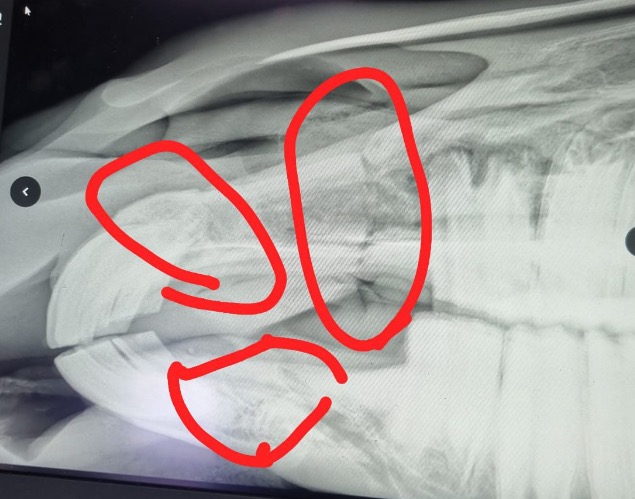

Toestemming voor dat spuitje heeft Jolijn niet gegeven. Djuna was ondanks de verwondingen en door de sedatie heen opgestaan toen ze eenmaal bevrijd was én ze liet levenslust zien. Ze is naar een kliniek gebracht voor onderzoek. Daar is vastgesteld dat haar bovenkaak twee- en onderkaak één keer gebroken is. Ook heeft ze een wond op haar achterbeen, dit is enkel een wond geen breuk! Jolijn heeft besloten Djuna een kans te geven, er is een team van specialisten samengesteld en de de kaak operatie (van meer dan 7 uren!) heeft inmiddels plaatsgevonden.